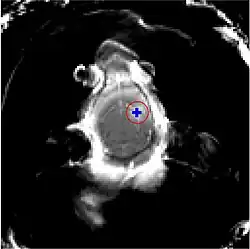

Der Fokus des Ultraschalls kann auf beliebige Areale im Gehirn gerichtet werden. Dadurch kann die Blut-Hirn-Schranke selektiv, auf bestimmte Hirnareale begrenzt, geöffnet werden. So können applizierte Wirkstoffe gezielt in diese Areale diffundieren.[140] Die behandelten Areale lassen sich durch eine simultan laufende Magnetresonanztomographie (MRT) genau verfolgen. Dabei dringt das für die MRT verwendete Kontrastmittel, beispielsweise Gadopentetat-Dimeglumin, nur durch die geöffneten Areale der Blut-Hirn-Schranke in das Gehirn ein. Diese Bereiche werden dadurch im MRT deutlich sichtbar hervorgehoben. Das hochpolare Gadopentetat-Dimeglumin ist nicht in der Lage die ungeöffneten Bereiche der Blut-Hirn-Schranke zu passieren.